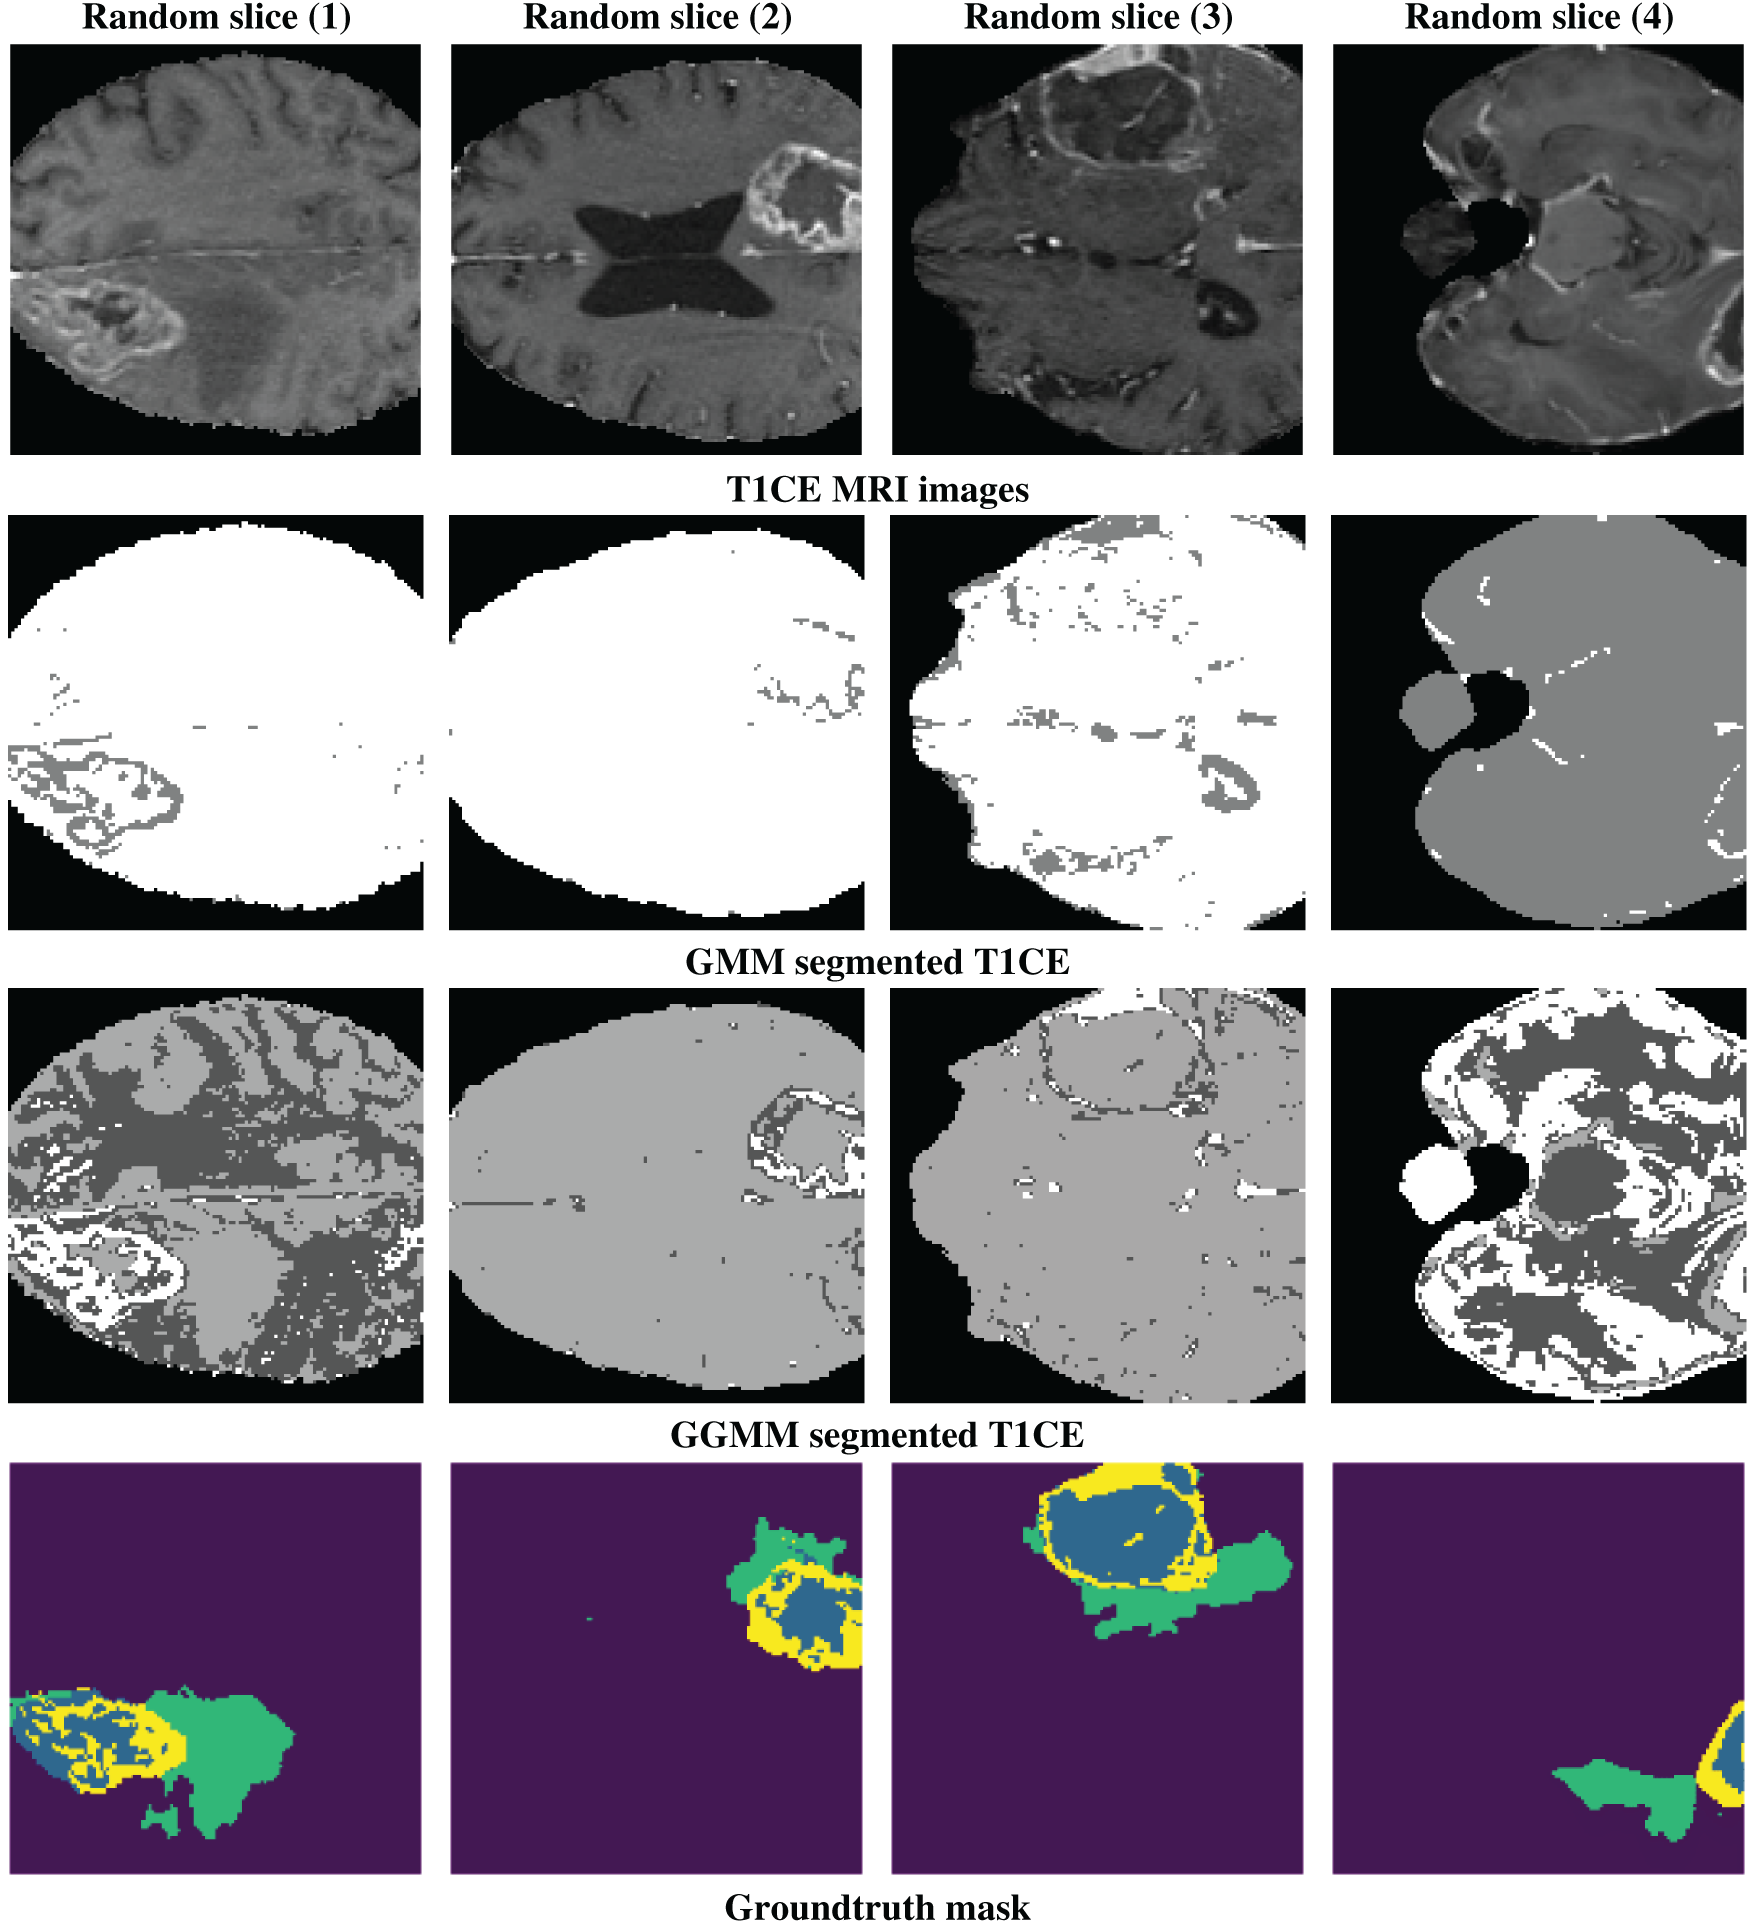

Fig. 1 shows the results of pre-processing (or pre-segmentation) for four randomly selected slices. The top row presents T1-weighted contrast-enhanced (T1CE) MRI images, which clearly distinguish the tumor from the surrounding tissue, demonstrating their effectiveness in delineating tumor boundaries and filled regions. The second row displays the segmentation results using the GMM, which attempts to differentiate tissue regions based on intensity but may struggle with complex contrast variations, leading to potential misclassifications. The third row demonstrates the use of the GGMM, which is an improvement over these boundaries because it enables a more diverse set of intensity distributions, enhancing identification of tumor areas such as the necrotic core, edema, and tumor-enhancing areas. The fourth row depicts the ground truth segmentation mask, a regular image that delineates the specific region of interest (e.g., necrotic core, edema, and enhancing tumor) in different colors, for reference to look at details presented by GGMM pre-segmented T1CE and how useful it is to utilize as model training input.

Figure 1: Example of a random slice: 1st line shows the T1CE modality, 2nd line shows the GMM-segmented T1CE, 3rd line shows the GGMM-segmented T1CE, and the 4th line shows the ground truth mask of the tumor regions